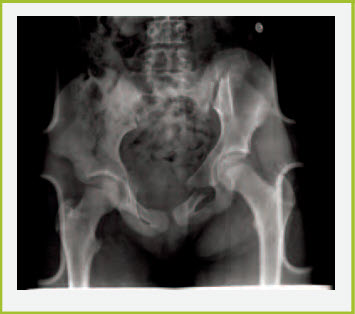

Pelvic fractures are a concern because they are generally the result of high-impact blunt trauma; blood loss can be significant. The pelvic ring may be fractured in a single place, which would be a stable fracture, or more commonly in multiple places, which could be an unstable fracture. Additional injuries associated with pelvic fractures include genitourinary and abdominal lesions, and vascular abnormalities (i.e. pelvic vein disruption). A sheet tightly wrapped around the pelvis may be the only temporizing measure for the unstable, bleeding pelvic fracture (Figure 11) until operative treatment is arranged.

Figure 11. Hip fracture